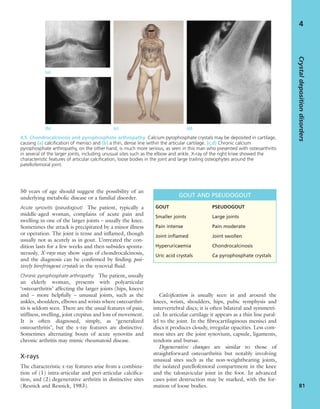

mal shape’ is so wide that variations should not auto-

matically be designated as deformities, and some

undoubted ‘deformities’ are not necessarily patholog-

ical; for example, the generally accepted cut-off points

for ‘abnormal’ shortness or tallness are arbitrary and

people who in one population might be considered

abnormally short or abnormally tall could, in other

populations, be seen as quite ordinary. However, if

one leg is short and the other long, no-one would

quibble with the use of the word ‘deformity’!